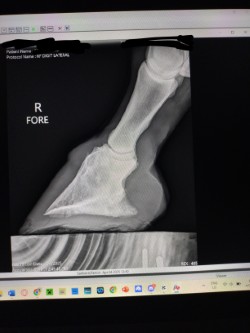

Rennie, a 2016 AQH, is a medical mystery; by all means, he shouldn't be standing, running, or jumping around the paddock. He was rescued in 2023 by a small family who help horses, skin and bones with a severe and constant limp in his right foreleg. We got him in February 2024, a great weight, but he still had a mysterious lameness that we couldn't figure out. After research, I found scoot boots. They took him from constant 3-4/5 lameness to a 1-2 lameness. Sound to be ridden (although he is just a paddock pet) We took x-ray at Texas A&M, the whole team was shocked, wondering how he is still alive with full fusion of his coffin, navicular and P3. His not only walking, but he is sound, happy, and a loving liberty pony. He came from a background of severe abuse. He has the physical and emotional scars of control-based training methods that left deep trauma: rope burns, whip marks, slashed legs, and twisted ears told a story of cruelty I wouldn’t wish on any animal. He had spent his final months before rescue in the auction pipeline.

I turned back to Rennie’s old farrier, the only one he and I trusted, but his flare-ups worsened, and without clear x-rays, we had little understanding of what was truly happening inside his hoof. I consulted my vet about quality of life, corrective shoeing, and every option we had left. When Texas A&M provided new x-rays, the truth was undeniable. His fusion was so severe that most professionals believed there was no choice but euthanasia. One corrective shoer refused to even see him, stating simply, "The horse should be put down."

But the team at Texas A&M saw what I saw—Rennie was defying the odds. Corrective shoeing wasn’t the answer. Traditional shoes would only add more stress, but Scoot Boots gave him freedom. They allowed his hoof to move as naturally as possible, relieving pressure without restricting movement. The specialists were amazed—not just at his ability to move, but at how much the boots had helped him. Without them, he wouldn’t be sound. Without them, I would have had to make the hardest decision.